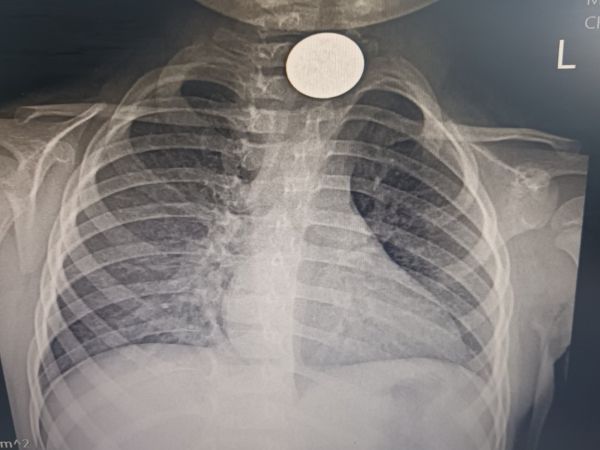

В УМБАЛ Бургас спасиха дете живяло с монета в хранопровода месец

...... Родителите се успокояват и няколко седмици Мелиса ходи на ясла, весела е, играе.Преди десетина дни малката внезапно започва да вдига висока температура, а сним

Лекари извадиха монета от 20 стотинки от 2 годишно момиченце която